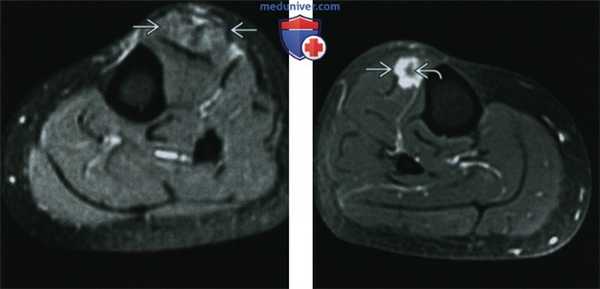

(Слева) МРТ Т2ВИ, режим подавления сигнала от жира, аксиальный срез: определяется мышечный узел в переднем ложе левой голени. Отмечается небольшое утолщение мышцы, а также новообразование, слегка яркое на Т2 ВИ. Они найдены у пациентки средних лет с саркоидозом, которая жаловалась на болезненные образования в голени.

(Справа) МРТ этой же пациентки, постконтрастные Т1 ВИ, режим подавления сигнала от жира, аксиальный срез. Саркоидные узлы в мышцах также визуализируются и в другой голени. При введении контраста были выявлены периферическое контрастирование и гипоинтенсивное вдавление; картина темной звезды характерна для узлов в мышцах при саркоидозе.

(Справа) МРТ этой же пациентки, постконтрастные Т1 ВИ, режим подавления сигнала от жира, аксиальный срез. Саркоидные узлы в мышцах также визуализируются и в другой голени. При введении контраста были выявлены периферическое контрастирование и гипоинтенсивное вдавление; картина темной звезды характерна для узлов в мышцах при саркоидозе. (Слева) МРТ, STIR, коронарный срез: у женщины средних лет, болеющей саркоидозом, определяется отек мышцы в ложе приводящих мышц с двух сторон. В зоне отека мышцы накапливается контраст. Картина визуализации на МРТ неспецифична.